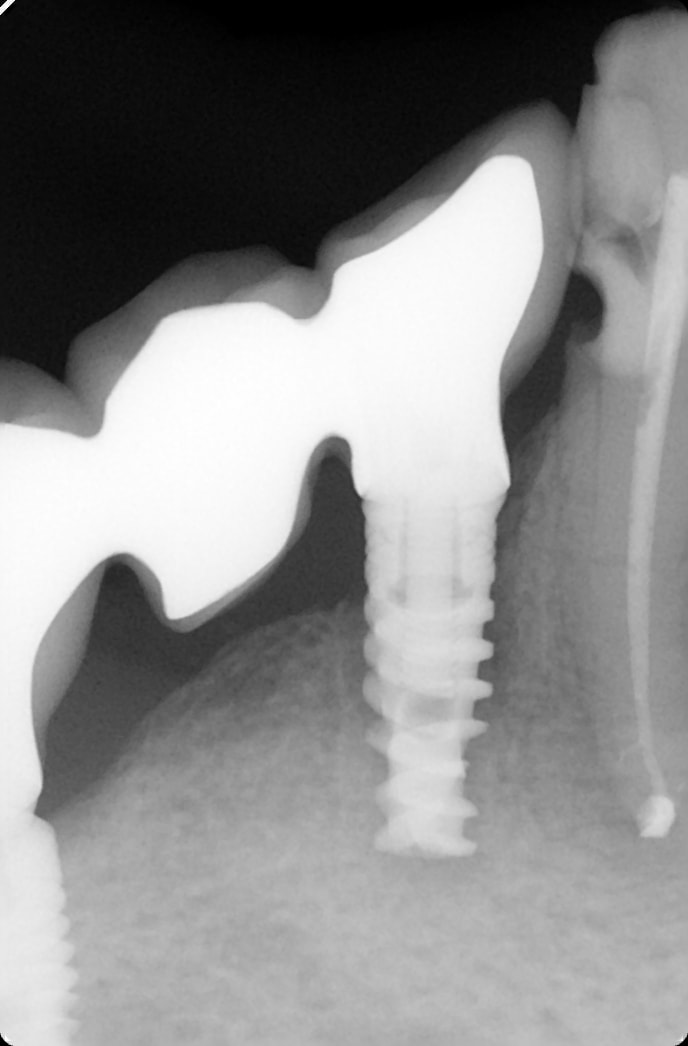

allez ne soyons pas sectaire que j'me dis. Si Enlaye le fait avec les dents, pourquoi pas avec un implant.

patient que je reçois en mai dernier , 93 ans, aucune hygiène, et beaucoup de soins dentaires. il vient pour autre chose, mais me parle aussi de son bridge mandibulaire droit qui bouge. je touche à peine et je me retrouve avec le bridge dans la main. le pilier distale est descellé, mais en mesiale j'ai l'implant qui vient avec le bridge. un coup de rincette avec la seringue du fauteuil, un peu de ciment en distal et je repose le tout dans l’alvéole. je revois le patient plus tard pour faire l'endo sur la 43..

la première radio date de mai, la deuxième a été faite cette semaine .

maintenant, l'augmentation de la densité osseuse est peut être une illusion du à la radio..